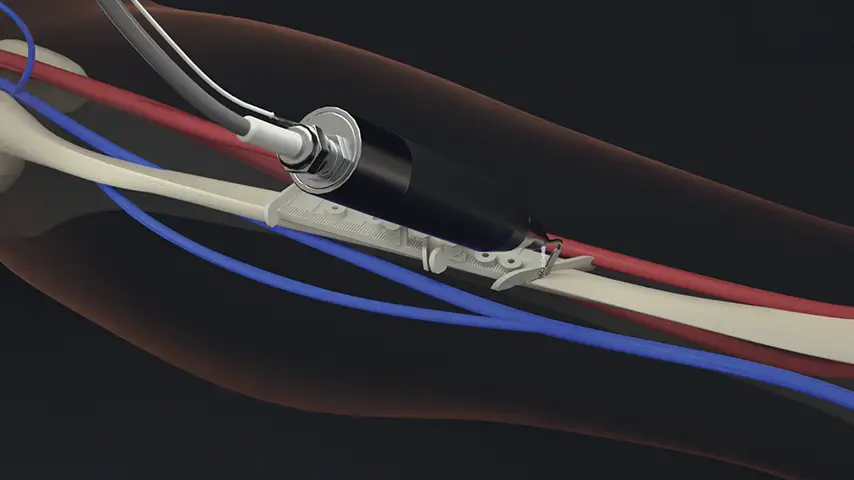

PIEZOSURGERY® plus

DESIGNED TO BE COMPLETE

PIEZOSURGERY® plus is the complete device: it is engineered to support an expansive range of surgical applications in ENT surgery.

Unmatched efficiency, precision, and performance delivered through two independent handpieces and channels.

PIEZOSURGERY® flex

DESIGNED TO BE FLEXIBLE

PIEZOSURGERY® flex is the essential device: with its perfect control, precision and ease of use it is your perfect start into an new era of bone surgery.